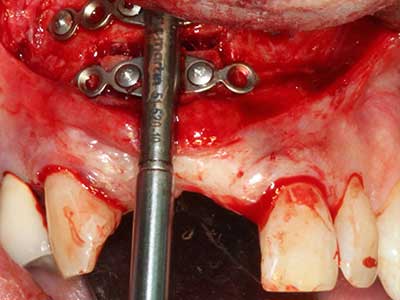

When surgical procedures are performed on bone in the immediate vicinity of sensitive structures such as blood vessels or nerves, rotary instruments pose a significant risk of iatrogenic injury. Piezoelectric devices can be helpful for preparation of bone covers and removal of hard tissue close to nerves, particularly for exposure of nerves after iatrogenic injury but also during nerve lateralization for resective and reconstructive procedures or implant placement (Fig. 17-20). Light contact between the piezotip and the nerve does not generally result in damage but proceeding incautiously with saw-like motions or attachments where a residual bone substrate remains may cause temporary or even permanent nerve damage. However, the risk of damage is considered to be substantially lower than when using saws or milling instruments (Pereira, Gealh et al. 2014).

As shown in the past, basically any bone surgery procedure represents a possible indication for piezo surgery. Thus preparation of the mobile segment in distraction osteogenesis (Fig. 23-25) and sandwich osteotomy uses special attachments without endangering the blood supply to the crestal section, which is essential for the success of both techniques (Gonzalez-Garcia, Diniz-Freitas et al. 2008).